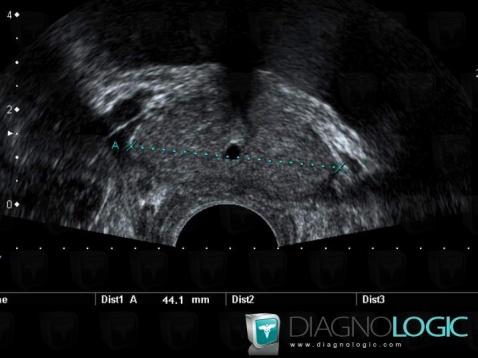

- Diagnostic Kyste de l'utricule, Localisation(s) Prostate, comportant les gammes Lésion prostatique kystique